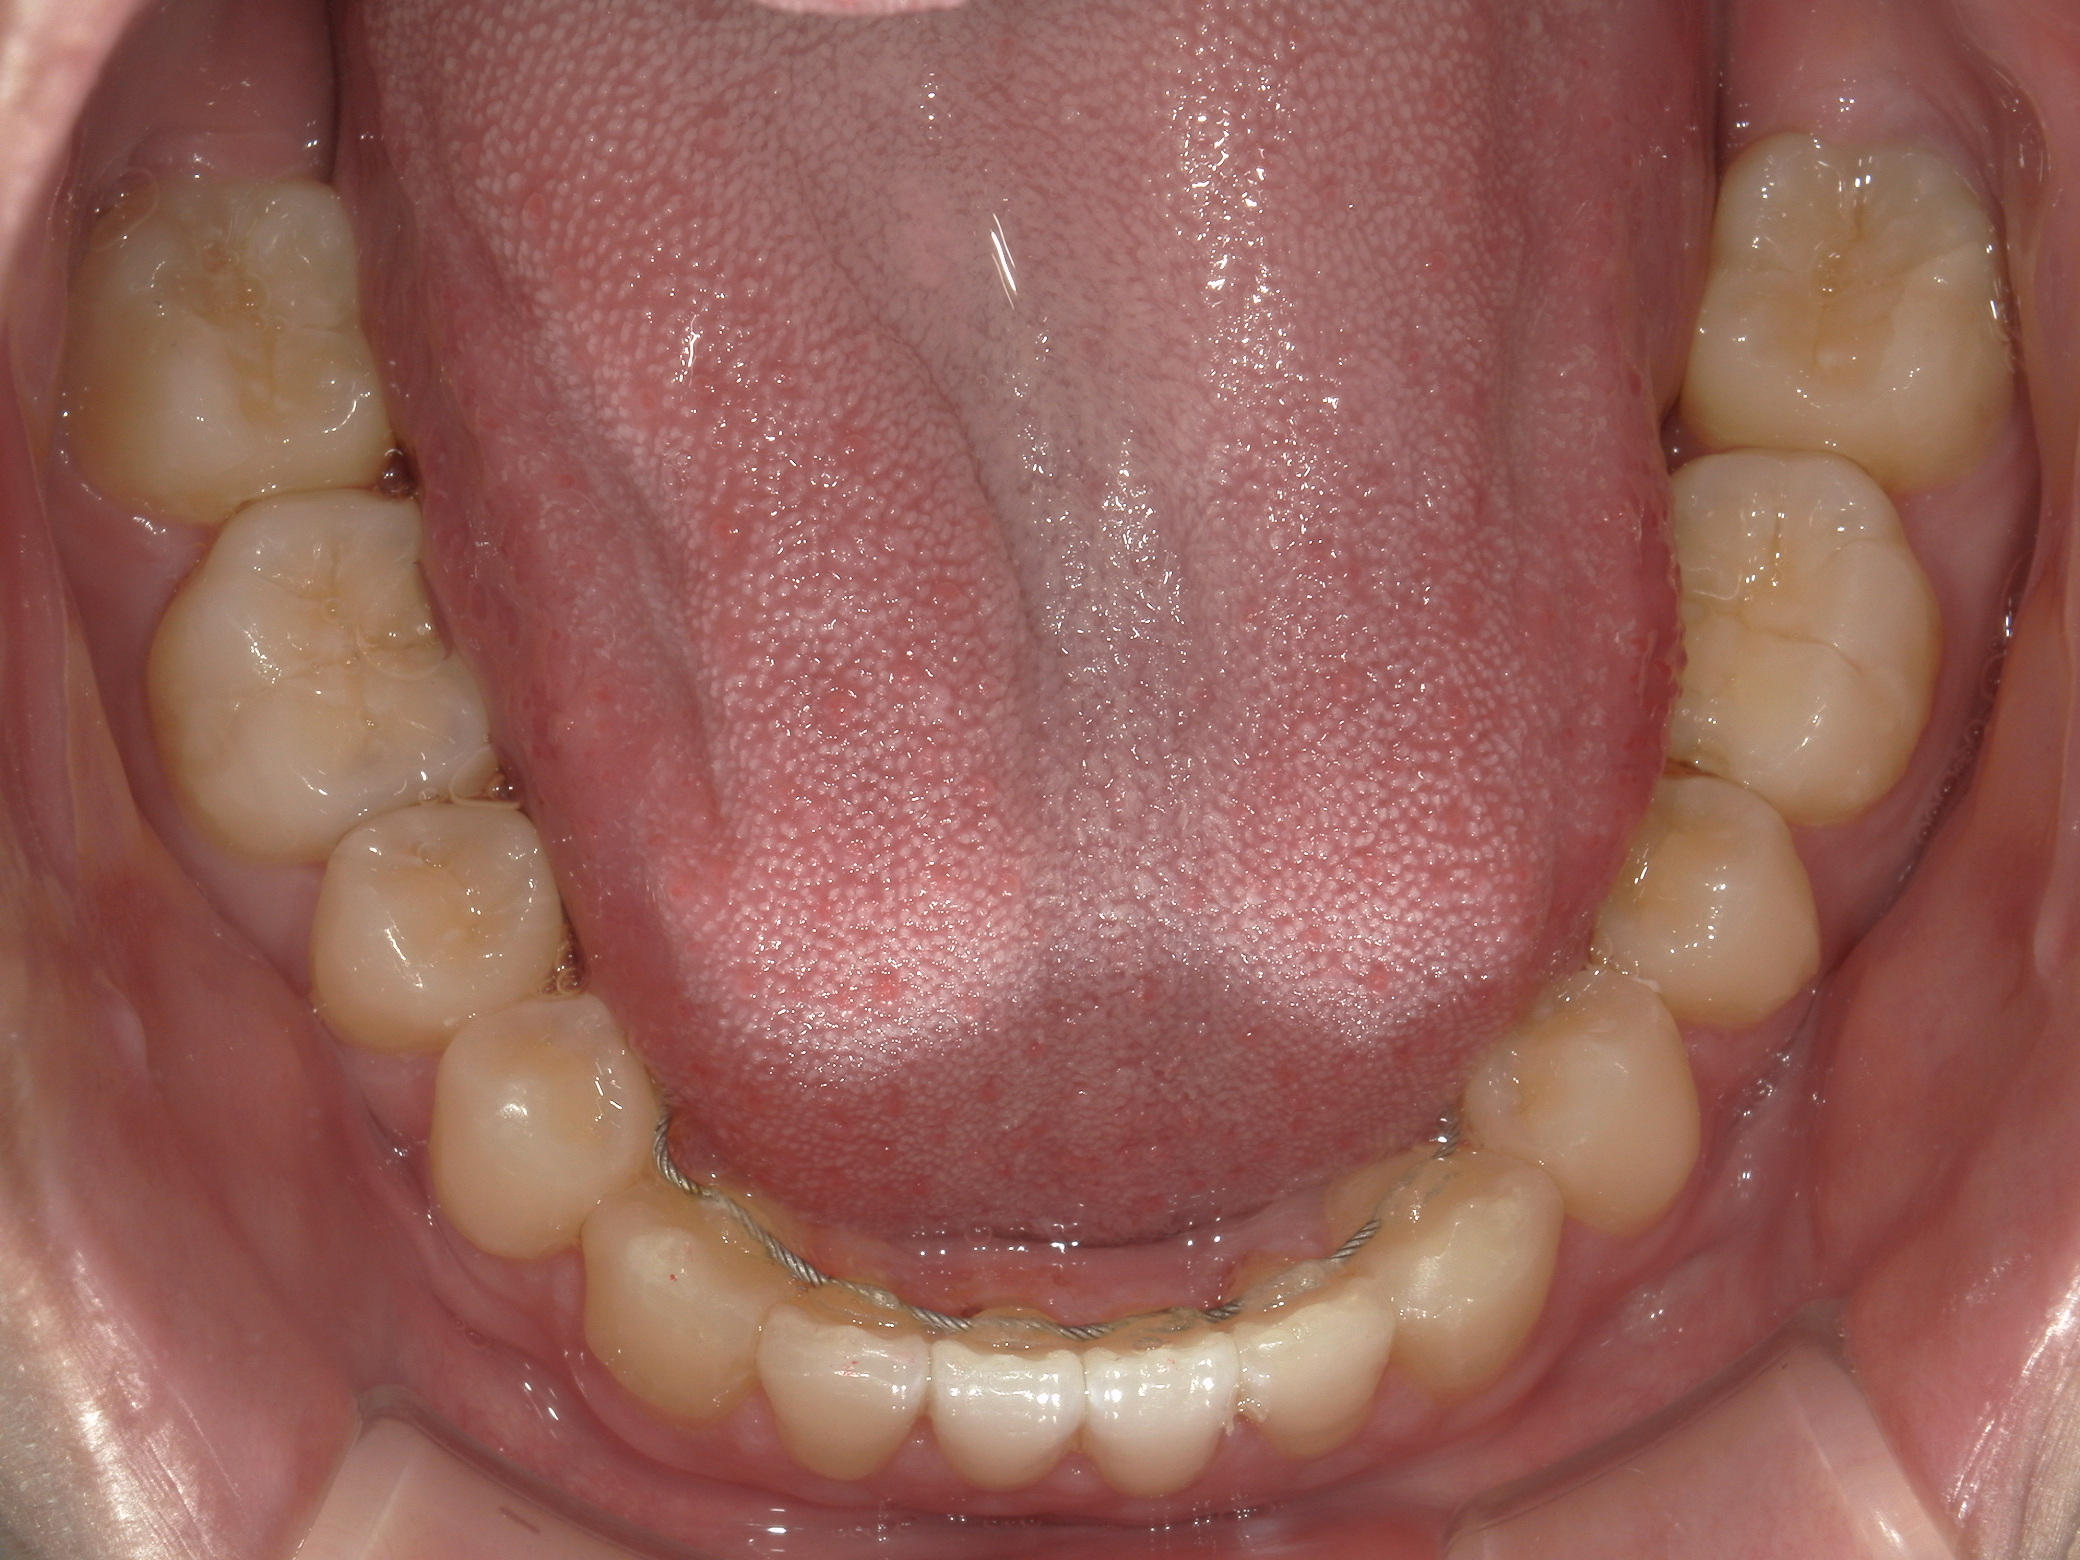

インビザライン矯正 症例(24)

主訴: 前歯の隙間が気になる。

左右上 第一小臼歯(2本)を抜歯。

スライスカットを併用。

カテゴリー : 隙間がある(空隙歯列)